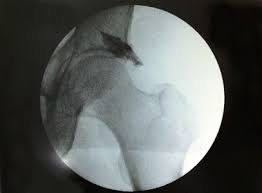

Cuando tiene un dolor glúteo profundo el médico puede pedirle que se realice algunas pruebas de imagen como la RMN y la tomografía computarizada para que pueda comprender la cantidad de daño al nervio. El síndrome que afecta más a las mujeres que a los hombres es poco común. El dolor o síndrome de los glúteos profundos es causado por la presión sobre el nervio que envía las señales de la sensación de dolor al cerebro. Este síndrome suele afectar al glúteo izquierdo porque nuestro cuerpo no es simétrico. Tengo desde hace mucho tiempo un dolor en el glúteo izdo sobre todo cuando camino lento pero no cuando lo hago más rápido raro no Llega a un punto que no tengo fuerza en la pierna y me quedo cojo. Por consiguiente al moverse el hueso sacro y las caderas ejercen presión sobre el piriforme izquierdo. El Síndrome Piramidal consiste en una contractura o espasmo involuntario del músculo piramidal. Hola doctor hace cosa de medio año me apareció sin motivo alguno un bulto del tamaño de un huevo de codorniz en el glúteo izquierdo en la parte interior. 1ª Parte Referencias Bibliográficas.

Esto ocurre cuando el músculo piriforme en los glúteos presiona el nervio ciático. Desde ese momento empecé a sentir un dolor muy fuerte en el glúteo. Por consiguiente al moverse el hueso sacro y las caderas ejercen presión sobre el piriforme izquierdo. Muchos pacientes acuden a mi consulta porque sienten un dolor casi siempre centrado en la ingle y la pierna por ejemplo al levantarla o con algunos giros. Esto ocurre cuando el músculo piriforme en los glúteos presiona el nervio ciático. El dolor del glúteo es un motivo de consulta frecuente que afecta a deportistas o a gente corriente de poca actividad. Les extraña porque no recuerdan haberse dado un golpe.